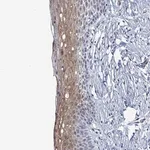

Prestige Antibodies® Powered by Atlas Antibodies의 친화 정제 항체로, WD repeat domain 70 (WDR70) 단백질을 인식합니다. Buffered aqueous glycerol 용액 형태로 제공됩니다.

- 타깃 단백질: WD repeat domain 70 (WDR70)

- 항원: WDR70 recombinant protein epitope signature tag (PrEST)

- 숙주: Rabbit

- 정제 방법: Affinity isolated antibody

- 단백질 발현 및 기능 연구

- 세포 내 단백질 위치 분석

- 웨스턴 블롯, 면역형광 등 다양한 면역분석 응용